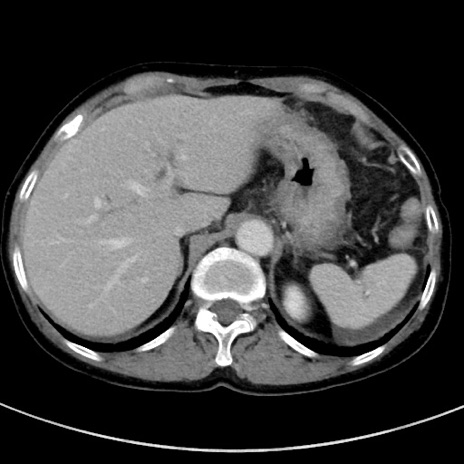

症例23(横断像)

【症例】70歳代女性

【主訴】下腹部痛・嘔吐

【現病歴】2日前より腹痛あり。昨日嘔吐あり。症状改善しないため来院。

【既往歴】胃GISTに対して胃部分切除後。

【身体所見】BT 37.1℃、BP 128/77mmHg、腹部:平坦・軟、下腹部に圧痛あり。

【データ】WBC 10200、CRP 0.31